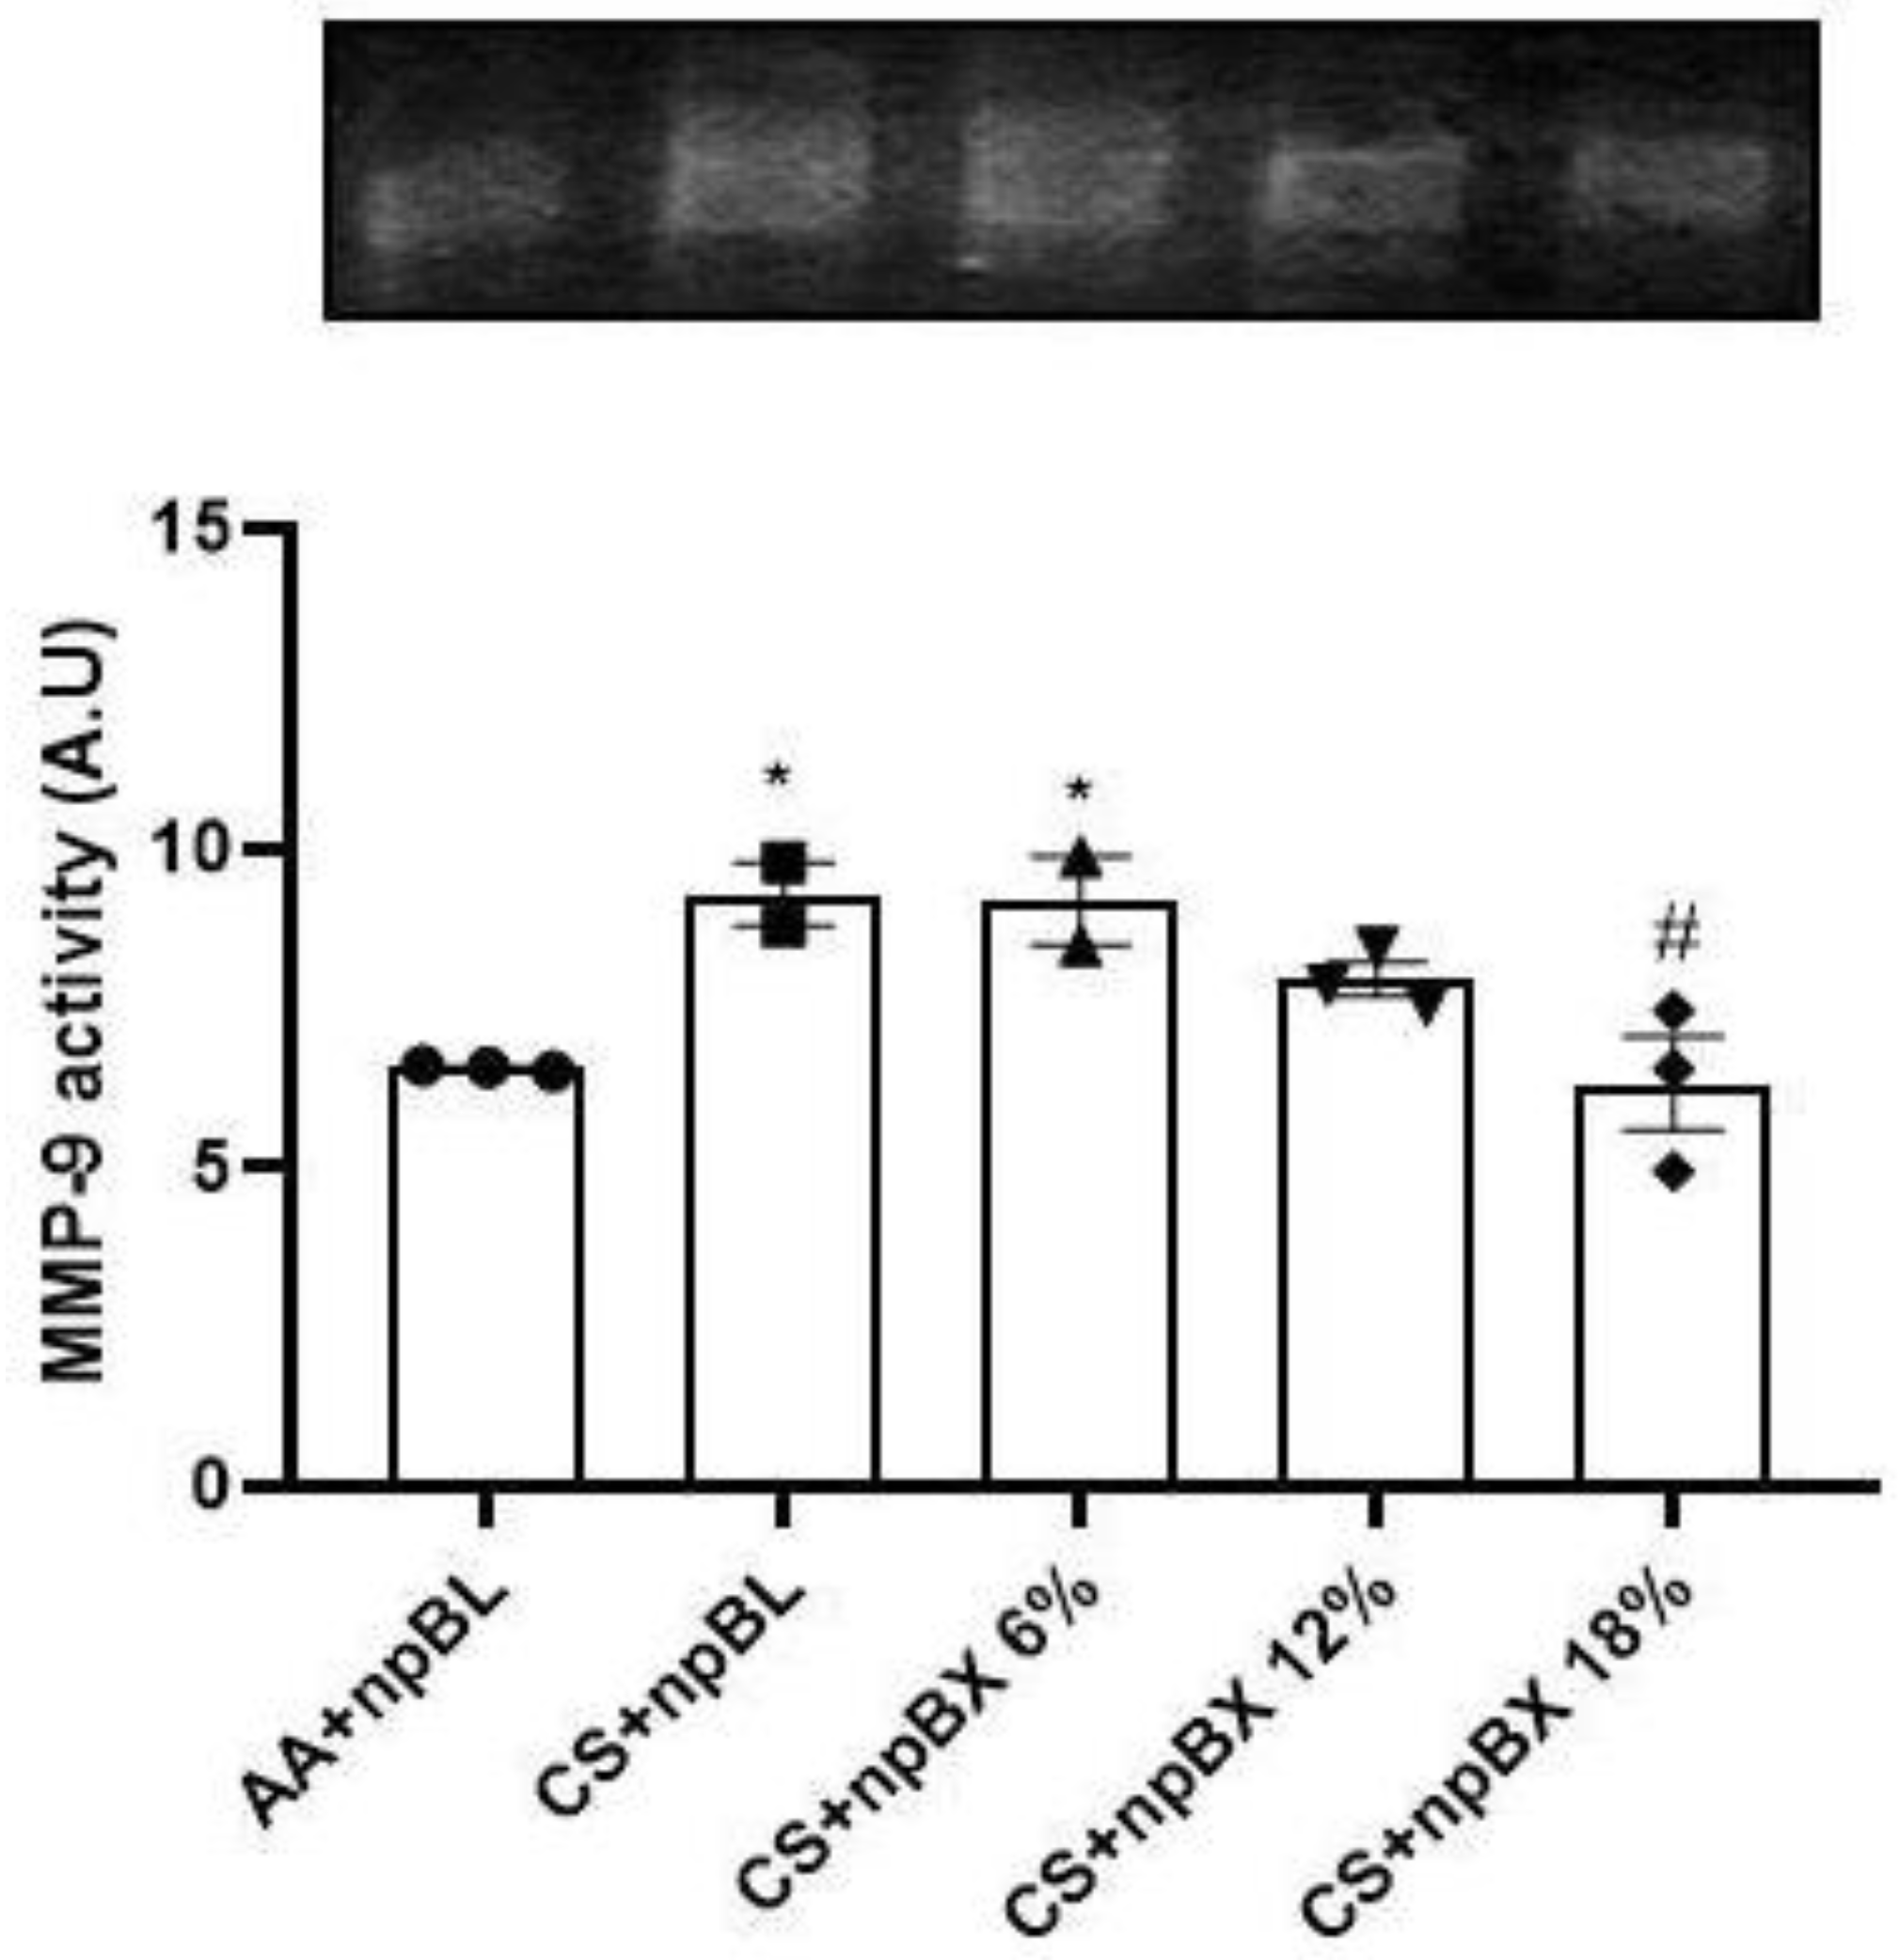

3.3.5. Bixin Nanoparticles Protected Lungs from MMP-9 Activity